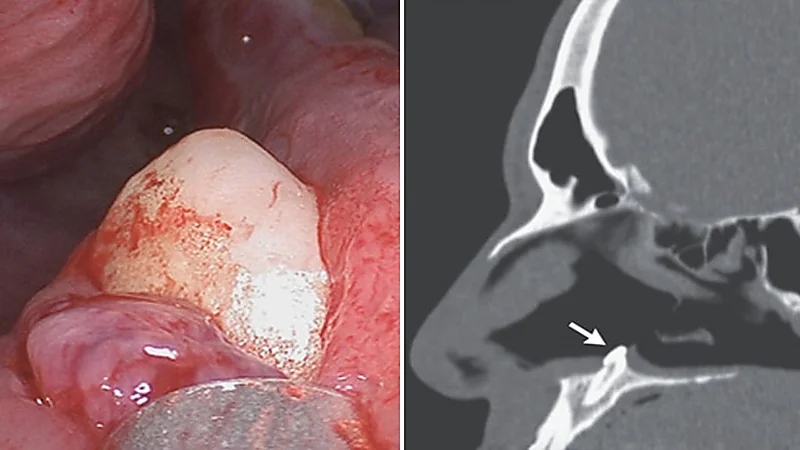

رجل يعاني من صعوبة التنفس بسبب نمو سن داخل أنفه